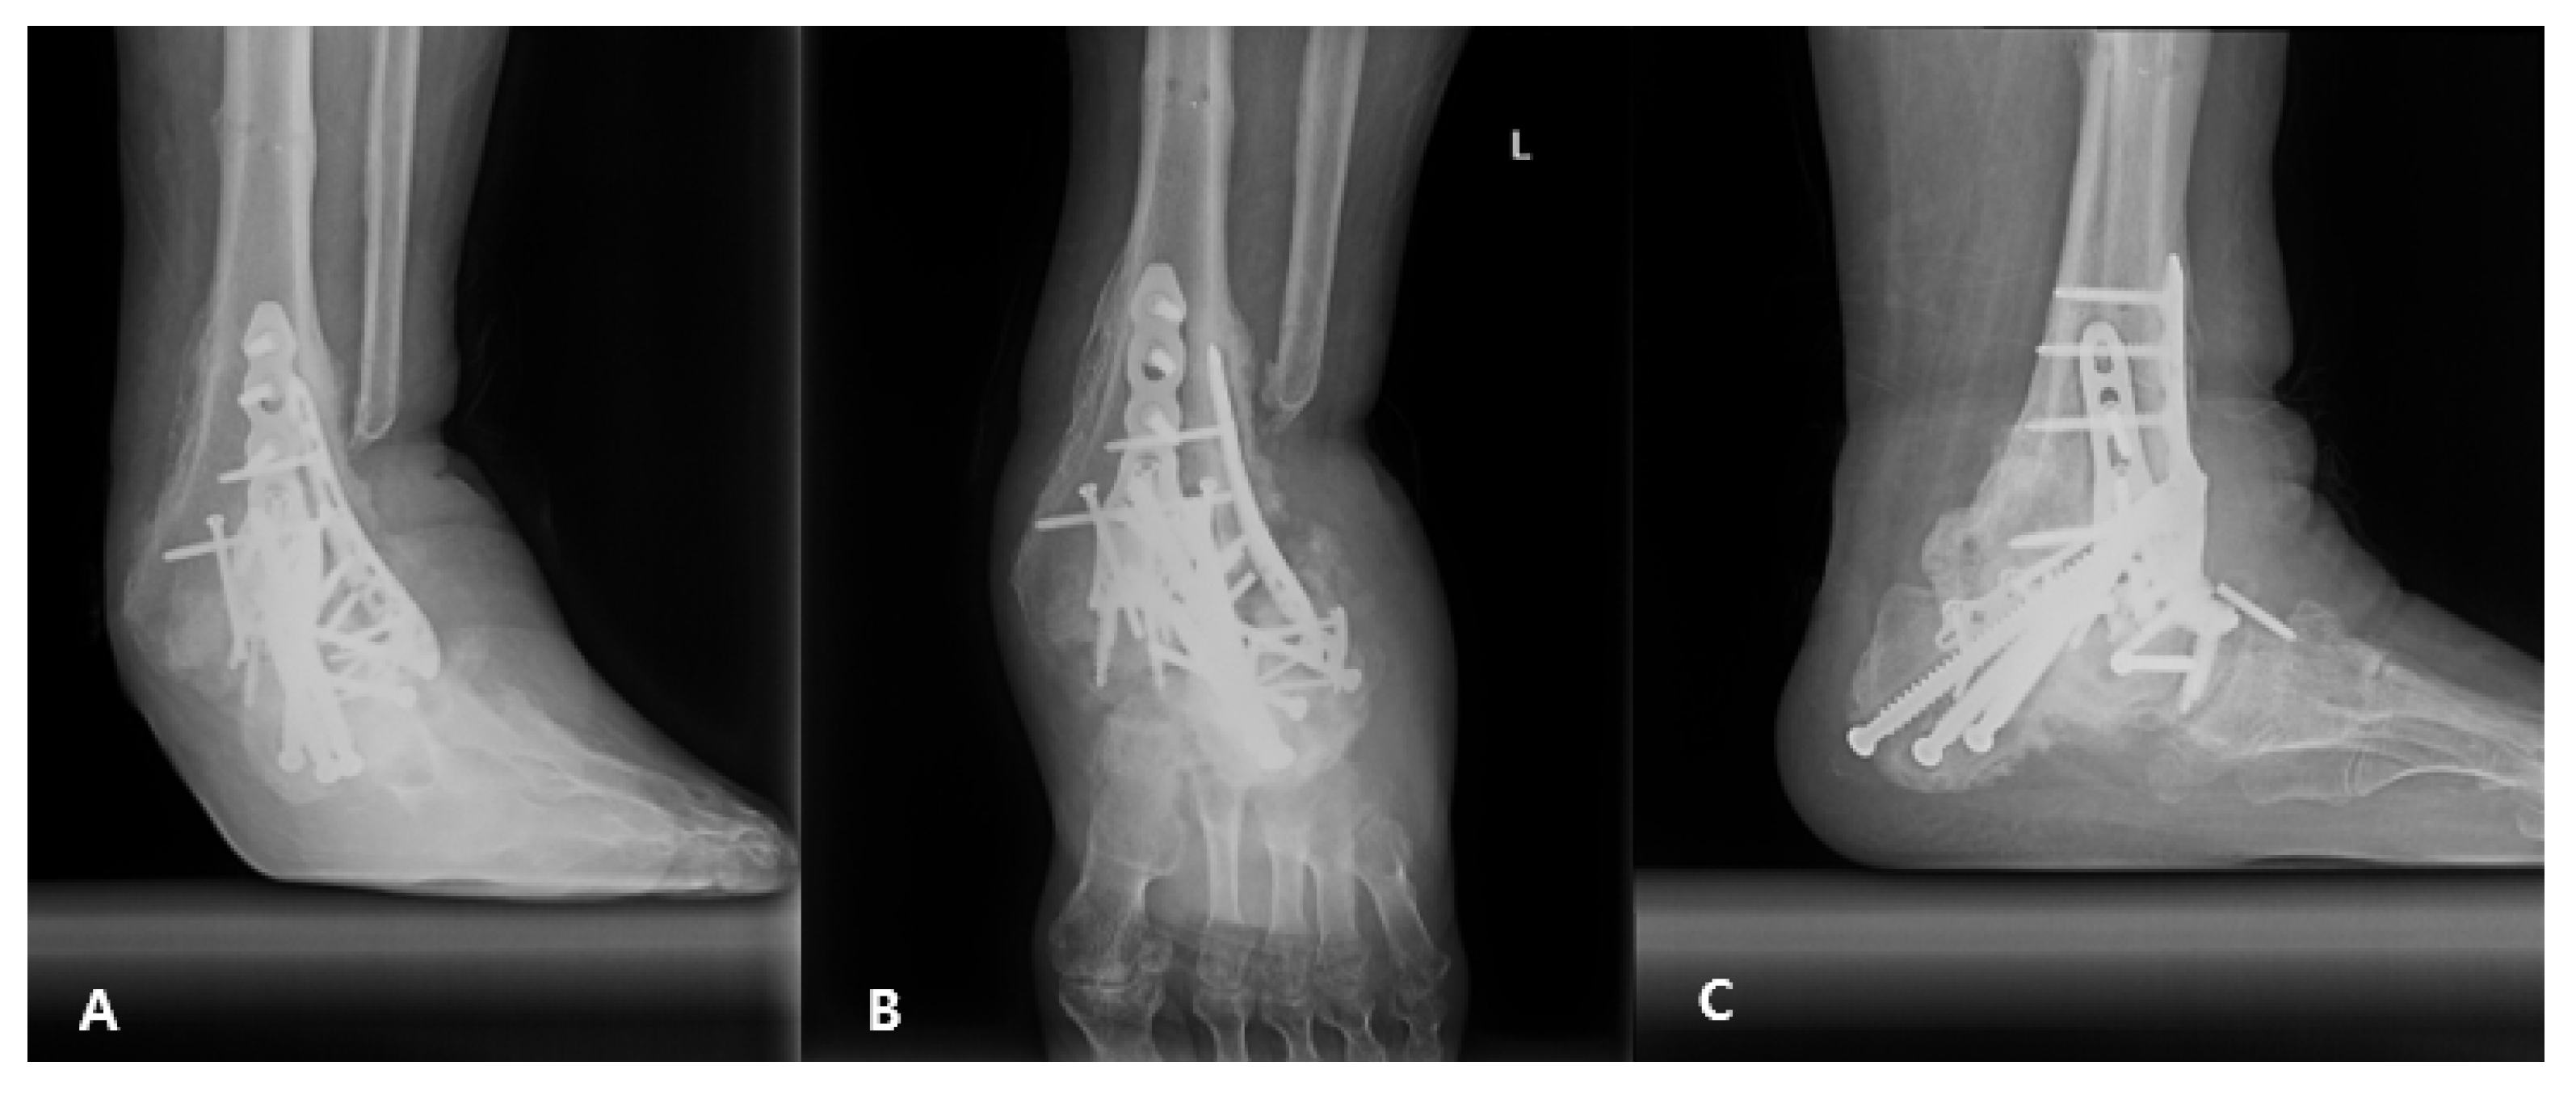

2.3. Postoperative Care